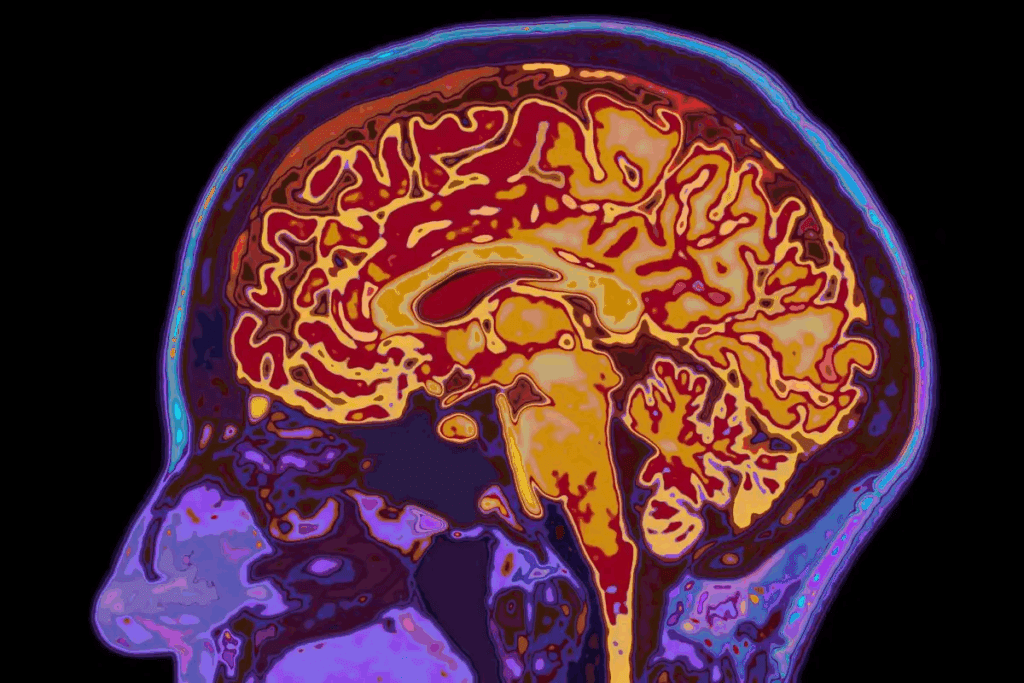

Learn about the essential hormones released from hypothalamus (e.g., TRH, GnRH) and their crucial role in regulating the pituitary gland clearly. The hypothalamus is a small part of the brain, about the size of a pea. It plays a big role in controlling many body functions by managing hormone secretion. It sits below the thalamus and above the pituitary gland, acting as the main control center for hormones and keeping the body balanced.

The hypothalamus is like the brain’s control center for hormones. It helps control the release of hormones that manage many body functions. It works closely with the pituitary gland, linking the nervous and endocrine systems.

The hypothalamus sits below the thalamus and above the pituitary gland. This spot is key for controlling hormone release. It has four main areas and three zones, each playing a role in its functions.